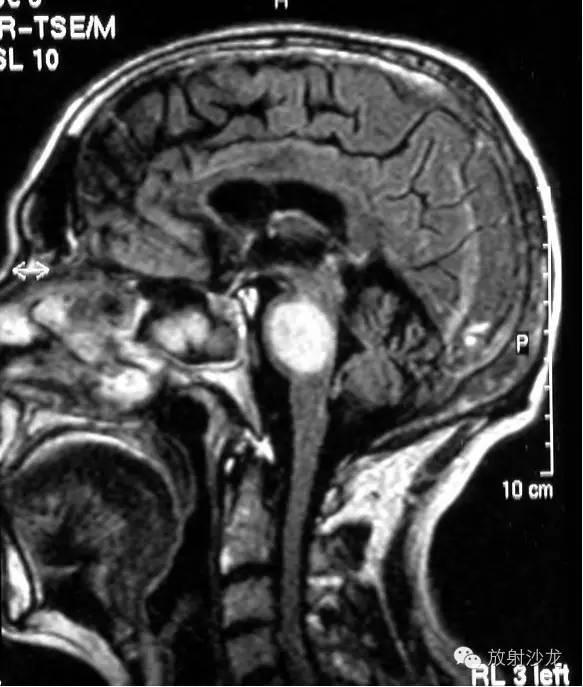

Balo concentric sclerosis. AYB, Axial T2-weighted and FLAIR images demonstrate alternating rings of hyperintensity and intermediate signal, suggesting variable degrees of demyelination. A moderate amount of surrounding edema is present.C, T1-weighted image shows multiple hypointense rings. D, Gadolinium-enhanced T1-weighted scan discloses heterogeneous enhancement. Reproduced from Hesselink.